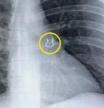

Se reveló que una anciana en el Lejano Oriente de Rusia había vivido durante 80 años con una aguja de 3 centímetros de largo en el cerebro, después de que los médicos hicieran el descubrimiento inesperado durante una tomografía computarizada.

Tiempos pasados. La escasez de alimentos prevaleció en toda la Unión Soviética durante la guerra, y muchas personas vivían en la pobreza extrema. "La aguja penetró en su lóbulo parietal izquierdo, pero no tuvo el efecto deseado: la niña sobrevivió", dijo el departamento de salud local.